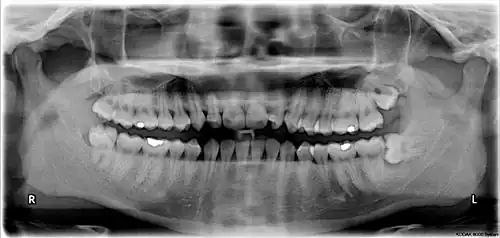

Wisdom teeth in the human mouth for permanent teeth. There are none in deciduous (children's) teeth. | |

The third molar, commonly called wisdom tooth, is the most posterior of the three molars in each quadrant of the human dentition. The age at which wisdom teeth come through (erupt) is variable,[1] but this generally occurs between late teens and early twenties.[2] Most adults have four wisdom teeth, one in each of the four quadrants, but it is possible to have none, fewer, or more, in which case the extras are called supernumerary teeth. Wisdom teeth may become stuck (impacted)[3] and not erupt fully, if there is not enough space for them to come through normally. Impacted wisdom teeth are still sometimes removed for orthodontic treatment, believing that they move the other teeth and cause crowding, though this is disputed.[4][5]

Wisdom teeth (often notated clinically as M3 for the third molar) have long been identified as a source of problems and continue to be the most commonly impacted teeth in the human mouth. Impaction of the wisdom teeth results in a risk of periodontal disease and dental cavities.[29] Impacted wisdom teeth lead to pathology in 12% of cases.[30]